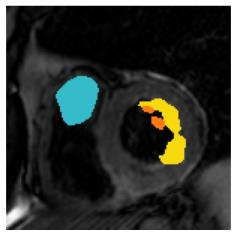

Although supervised deep-learning has achieved promising performance in medical image segmentation, many methods cannot generalize well on unseen data, limiting their real-world applicability. To address this problem, we propose a deep learning-based Bayesian framework, which jointly models image and label statistics, utilizing the domain-irrelevant contour of a medical image for segmentation. Specifically, we first decompose an image into components of contour and basis. Then, we model the expected label as a variable only related to the contour. Finally, we develop a variational Bayesian framework to infer the posterior distributions of these variables, including the contour, the basis, and the label. The framework is implemented with neural networks, thus is referred to as deep Bayesian segmentation. Results on the task of cross-sequence cardiac MRI segmentation show that our method set a new state of the art for model generalizability. Particularly, the BayeSeg model trained with LGE MRI generalized well on T2 images and outperformed other models with great margins, i.e., over 0.47 in terms of average Dice. Our code is available at https://zmiclab.github.io/projects.html.